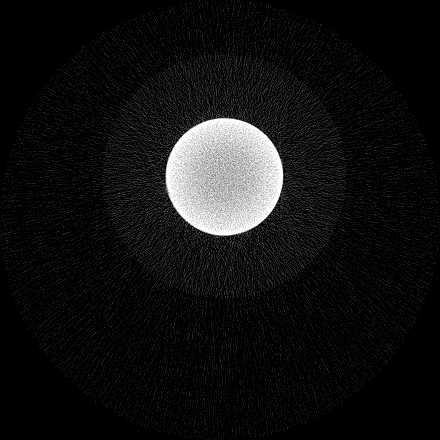

Figure 7 shows a single slice spectral reconstruction of the Mg scaffold. Due to low atomic number of Mg (Z = 12) compared to Ti (Z = 22), the results did not exhibit any significant beam hardening effects. Low energy reconstruction shows good spatial information while high energy ranges are limited by photon noise. In scans involving smaller samples made from low-Z materials like Al or Mg, acquiring low energy quanta in CSM provide high spatial information with minimum or no beam hardening effects. Figure 8 illustrates a single slice spectral reconstruction of the Ti mesh. Similar to the Ti scaffold, streaks are less pronounced in the mid and high energy ranges.

Refer to caption

(a) 15 to 80 keV

(b) 35 to 80 keV

(c) 55 to 80 keV

(d) 62 to 80 keV

Figure 7: Spectral reconstruction of Mg scaffold. Low energy ranges provide good spatial resolution while high energy ranges are limited by photon noise.